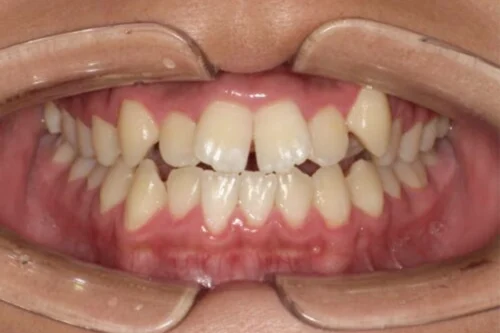

マイオブレース 小児歯科 症例集 矯正治療

前歯の噛み合わせが逆…

「歯並びの相談」から始まった、お子さんの噛み合わせの経過

「子どもの歯並び、これって大丈夫かな……